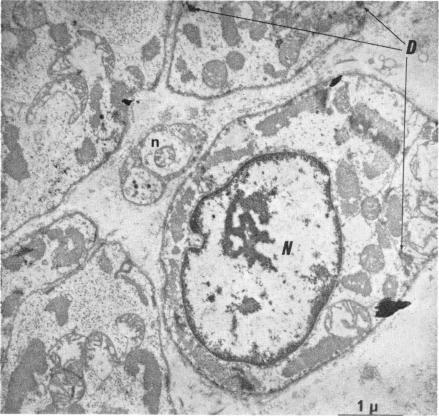

Cardiac innervation: anatomic and pharmacologic relations.

Bull N Y Acad Med. 1967 Dec;43(12):1041-86.